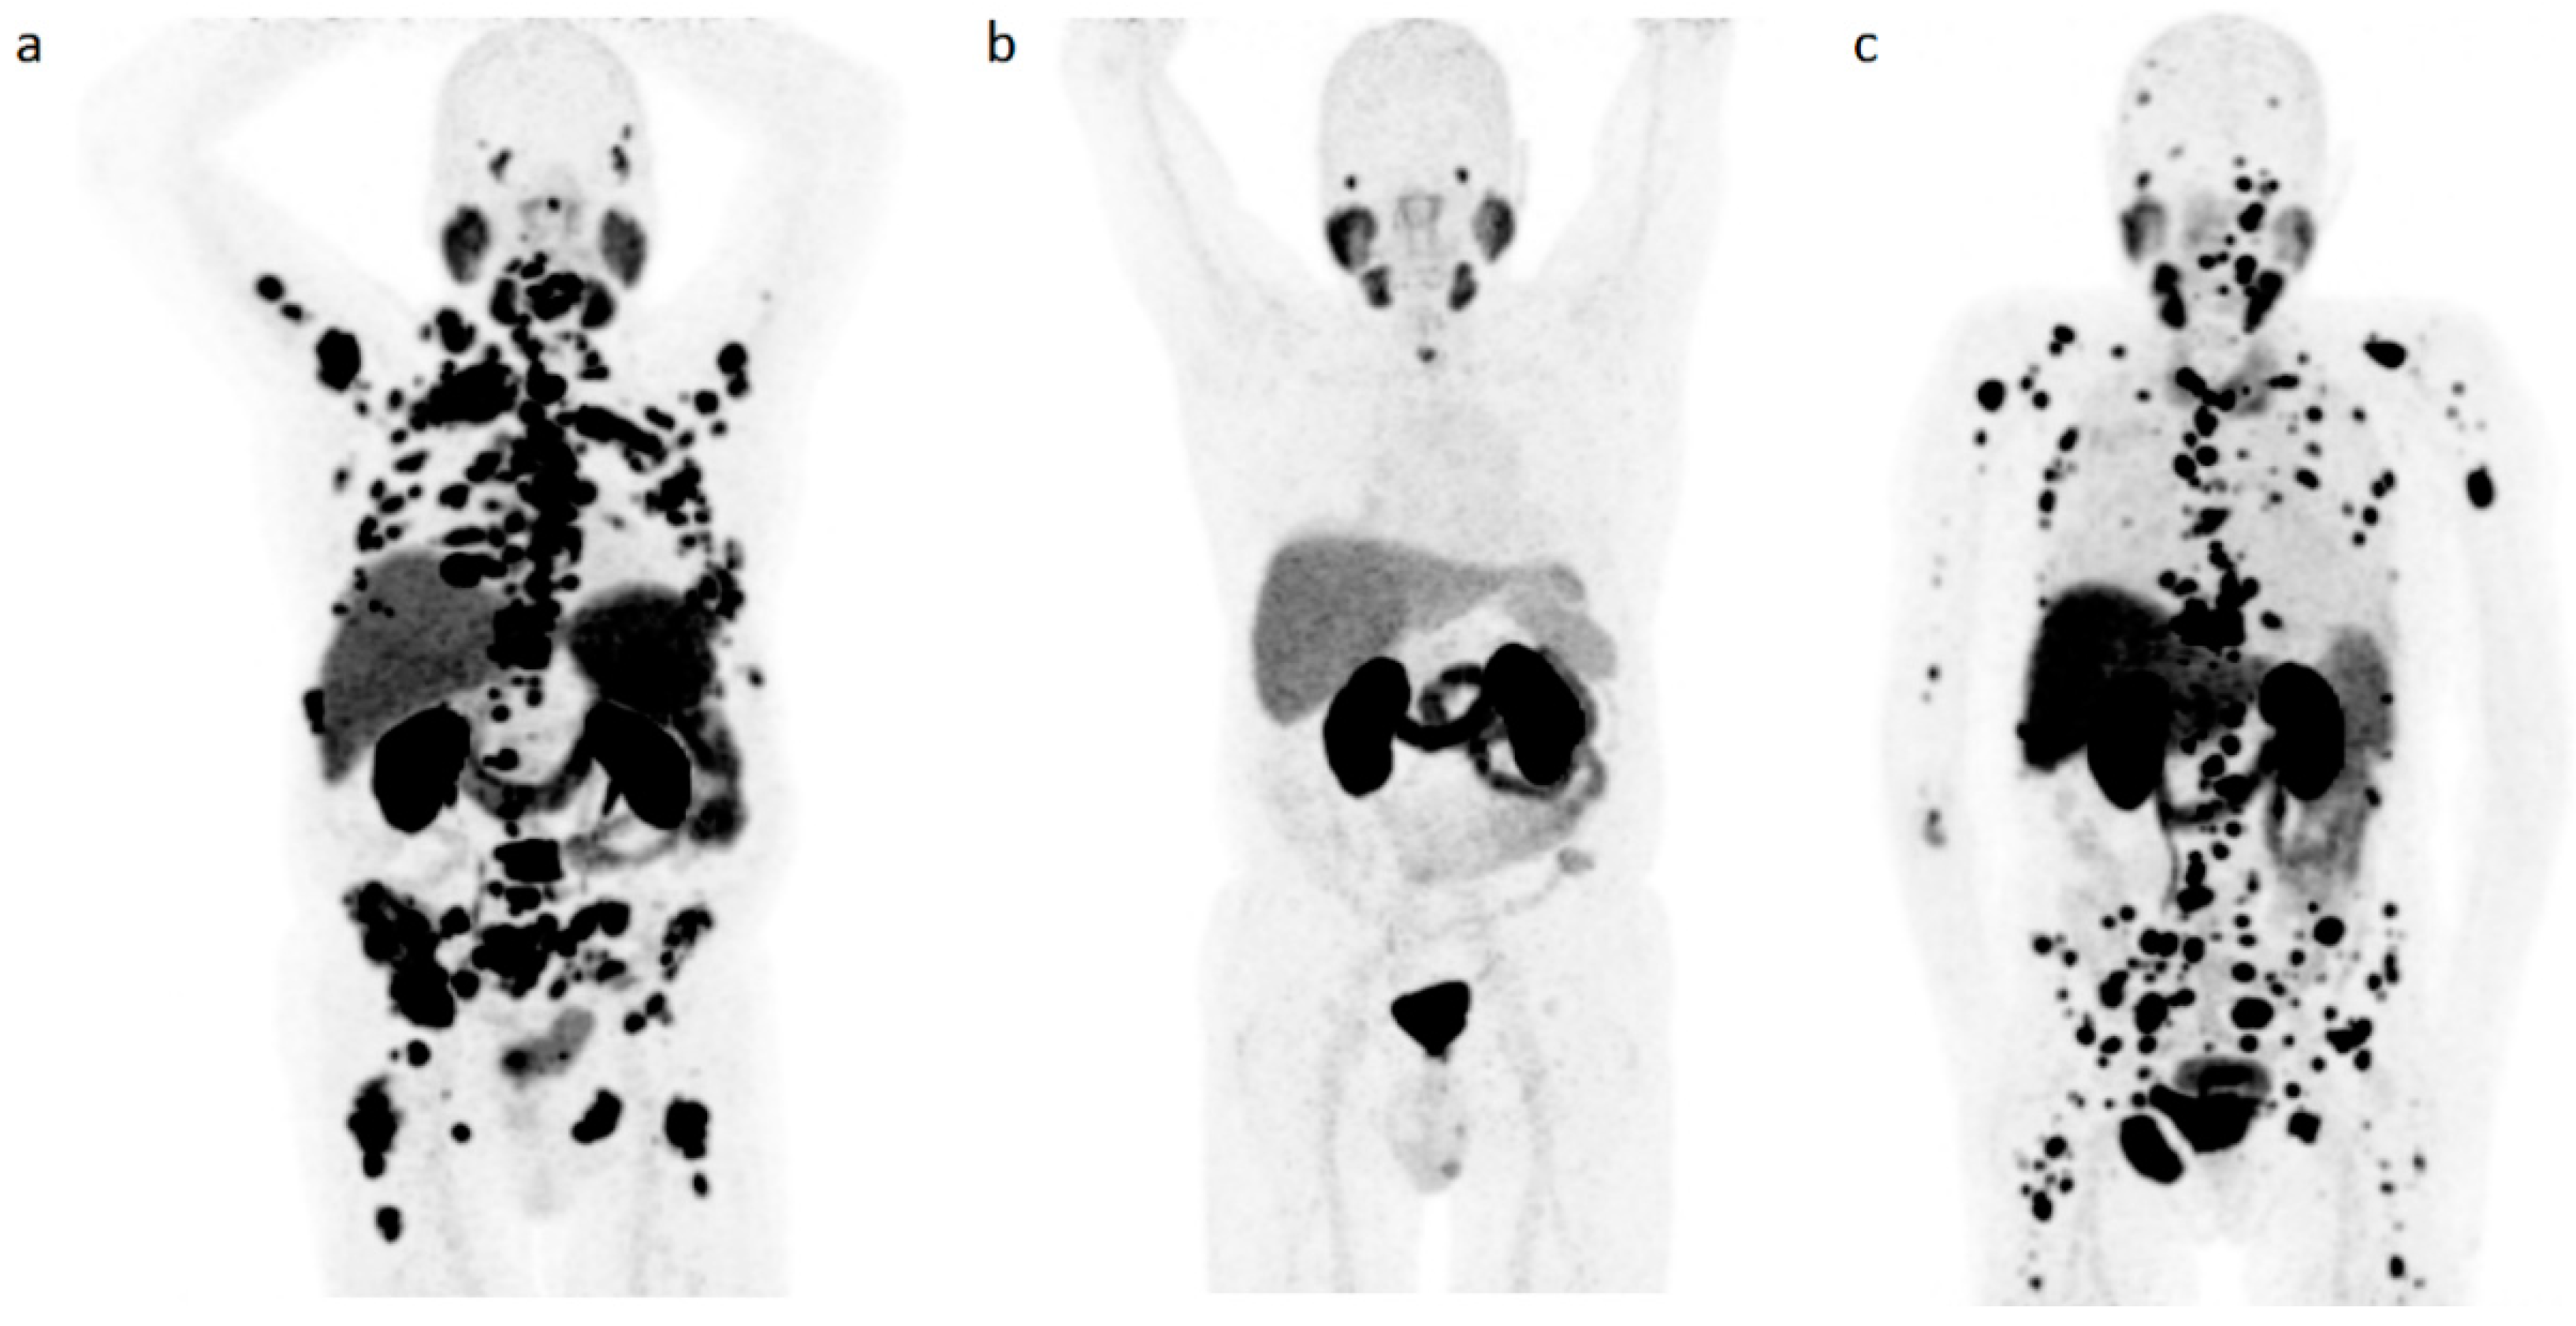

Competition (‘Steal’ Phenomenon) between [68Ga]Ga-PSMA-11 Uptake in Prostate Tumor Tissue Versus Healthy Tissue

- Filss, C.; Heinzel, A.; Miiller, B.; Vogg, A.T.J.; Langen, K.J.; Mottaghy, F.M. Relevant tumor sink effect in prostate cancer patients receiving 177Lu-PSMA-617 radioligand therapy. Nuklearmedizin 2018, 57, 19–25. [Google Scholar] [CrossRef]

- Gaertner, F.C.; Halabi, K.; Ahmadzadehfar, H.; Kurpig, S.; Eppard, E.; Kotsikopoulos, C.; Liakos, N.; Bundschuh, R.A.; Strunk, H.; Essler, M. Uptake of PSMA-ligands in normal tissues is dependent on tumor load in patients with prostate cancer. Oncotarget 2017, 8, 55094–55103. [Google Scholar] [CrossRef]

- Werner, R.A.; Bundschuh, R.A.; Bundschuh, L.; Lapa, C.; Yin, Y.; Javadi, M.S.; Buck, A.K.; Higuchi, T.; Pienta, K.J.; Pomper, M.G.; et al. Semiquantitative Parameters in PSMA-Targeted PET Imaging with [18F]DCFPyL: Impact of Tumor Burden on Normal Organ Uptake. Mol. Imaging Biol. 2020, 22, 190–197. [Google Scholar] [CrossRef]